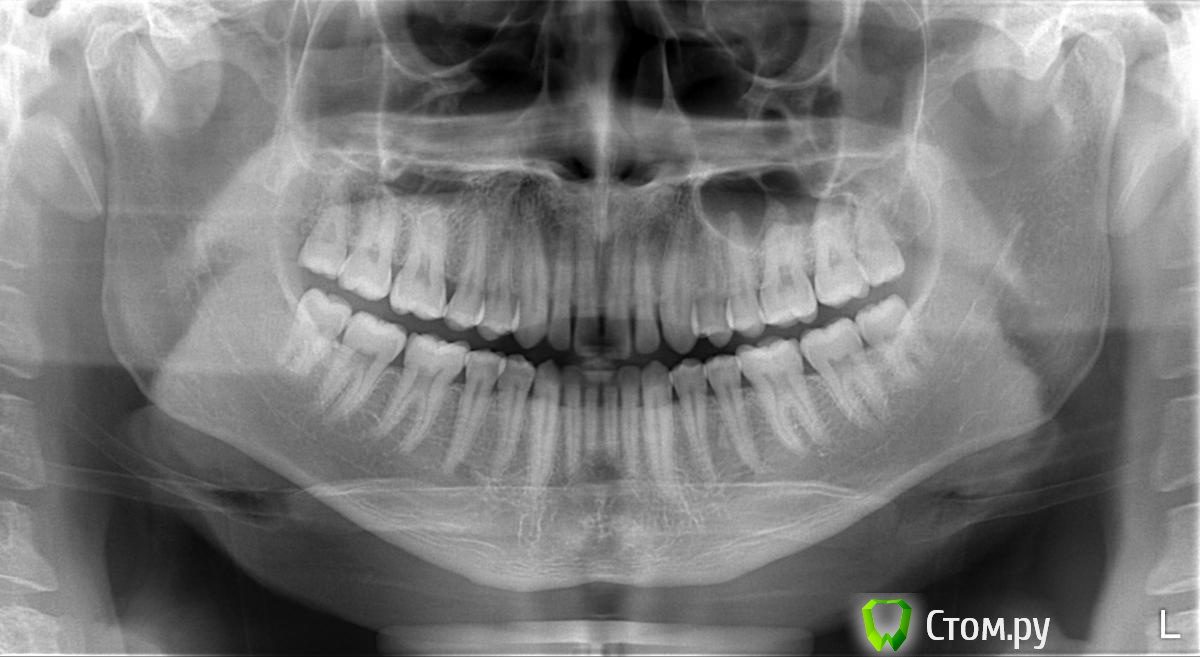

Mono22 Опубликовано 21 ноября, 2014 Поделиться Опубликовано 21 ноября, 2014 Здравствуйте. Скажите, пожалуйста, нет ли скрытого кариеса, все ли в порядке? Ссылка на комментарий

shishok Опубликовано 21 ноября, 2014 Поделиться Опубликовано 21 ноября, 2014 Явного нет,при очном осмотре проверить фиссуры и передние поверхности нижних пятых. 1 Ссылка на комментарий

Mono22 Опубликовано 21 ноября, 2014 Автор Поделиться Опубликовано 21 ноября, 2014 Спасибо. А белые пятка между зубами, это что? Ссылка на комментарий

IvanK Опубликовано 22 ноября, 2014 Поделиться Опубликовано 22 ноября, 2014 это что? это все в порядке) Ссылка на комментарий

shishok Опубликовано 22 ноября, 2014 Поделиться Опубликовано 22 ноября, 2014 На контактных поверхностях?Это наслаивается эмаль от соседних зубов(получается более контрастно). 1 Ссылка на комментарий